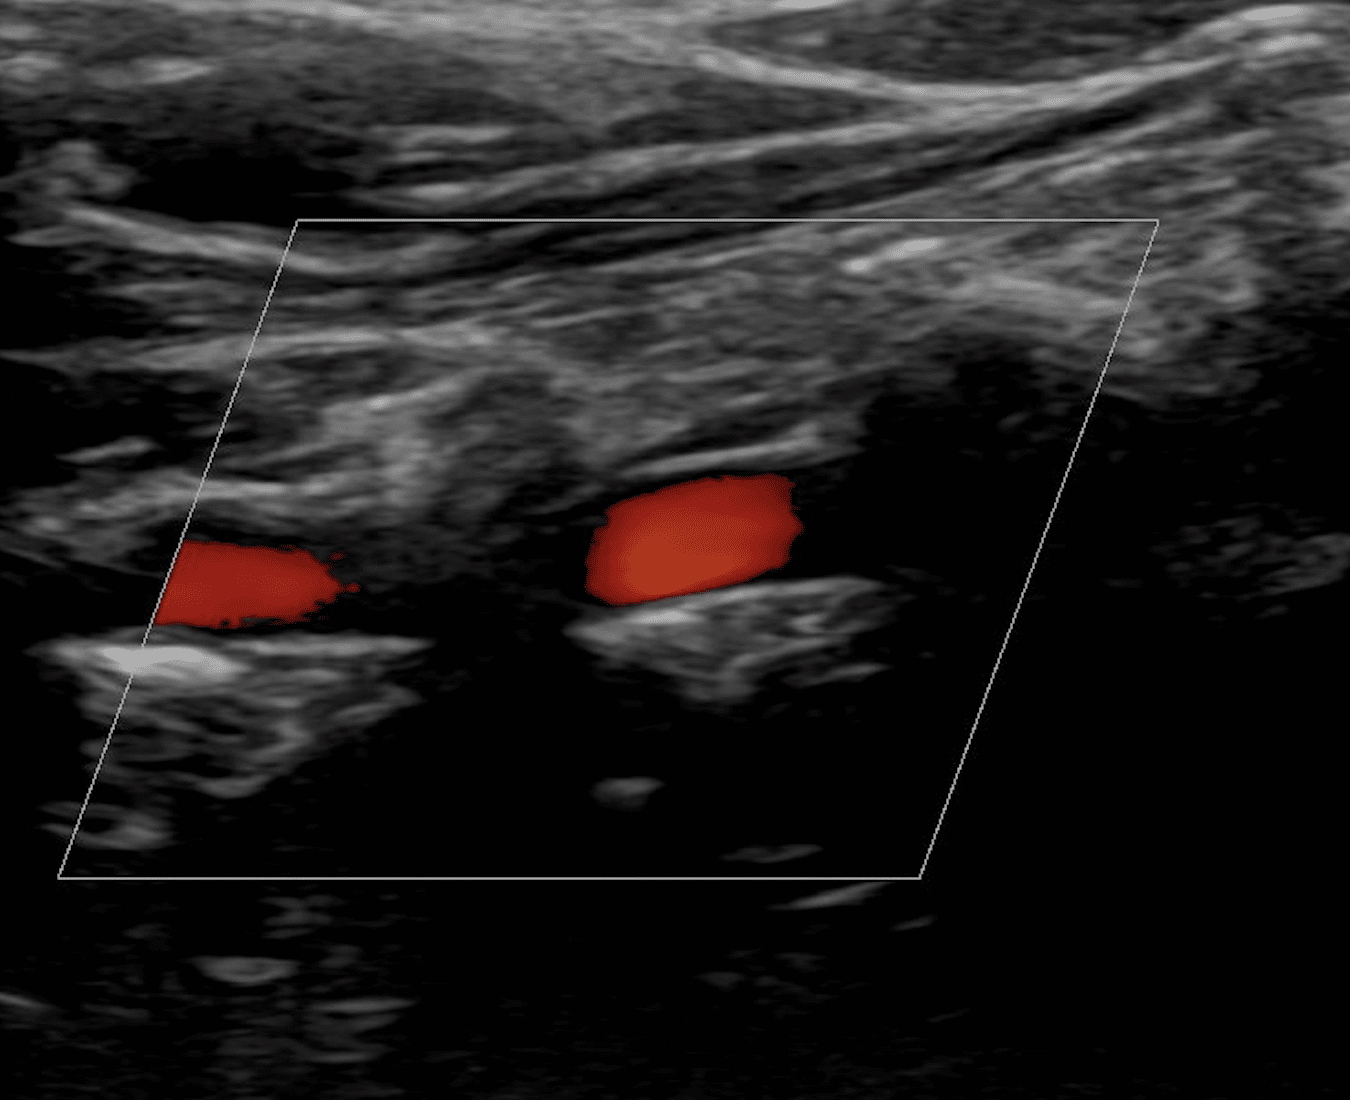

Ultraschall Halsschlagadern

| 3 Gespräch 15min | 3 | 26,22 |

| 410 Sonographie ein Organ | 2,3 | 26,81 |

| 420 3 weitere Organe | 2,3 | 10,72 |

| 645 Doppler/Duplex | 2,5 | 94,72 |

| 75 Ausführlicher Befundbericht | 2,3 | 17,43 |

| 175,90 |